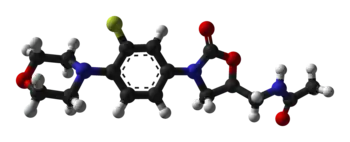

| 3D model (JSmol) | |

Linezolid, like other oxazolidinones, is a bacterial protein synthesis inhibitor and a weak, non-selective, reversible monoamine oxidase inhibitor.[3][99] As a protein synthesis inhibitor, linezolid stops the growth and reproduction of bacteria by disrupting translation of messenger RNA (mRNA) into proteins in bacterial ribosomes.[3] Linezolid inhibits translation at the first step of protein synthesis, initiation,[3][100] unlike most other protein synthesis inhibitors, which inhibit elongation.[8][60] It does so by preventing the formation of the initiation complex, composed of the 30S and 50S subunits of the ribosome, tRNA, and mRNA. Linezolid binds to the 23S portion of the 50S subunit (the center of peptidyl transferase activity),[3][100] close to the binding sites of chloramphenicol, lincomycin, and other antibiotics. Due to this unique mechanism of action, cross-resistance between linezolid and other protein synthesis inhibitors is highly infrequent or nonexistent.[21][52]

In 2008, the crystal structure of linezolid bound to the 50S subunit of a ribosome from the archaean Haloarcula marismortui was elucidated by a team of scientists from Yale University and deposited in the Protein Data Bank.[101] Another team in 2008 determined the structure of linezolid bound to a 50S subunit of Deinococcus radiodurans. The authors proposed a refined model for the mechanism of action of oxazolidinones, finding that linezolid occupies the A site of the 50S ribosomal subunit, inducing a conformational change that prevents tRNA from entering the site and ultimately forcing tRNA to separate from the ribosome.[102]